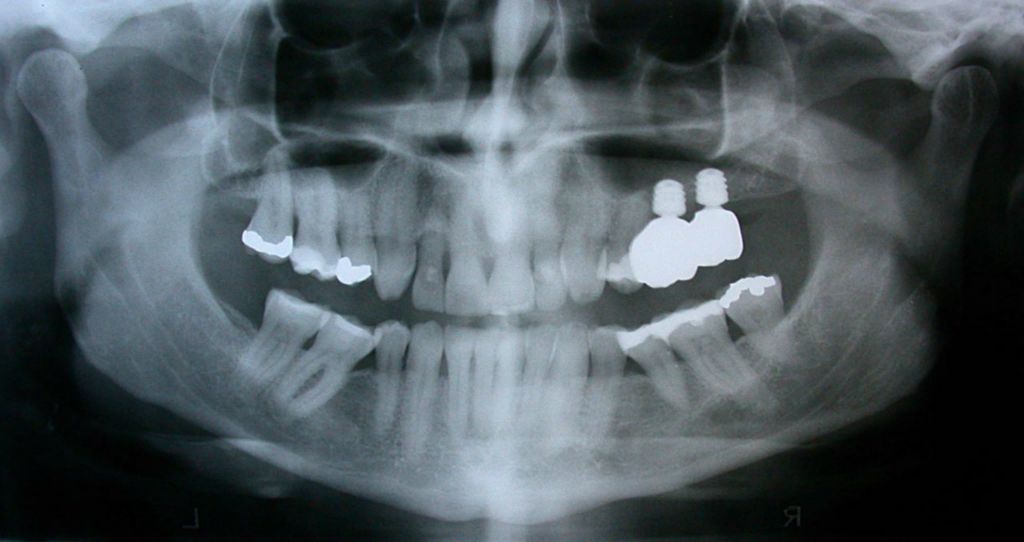

Zirconia bridge on Southern DC Implants

Tooth Replacement